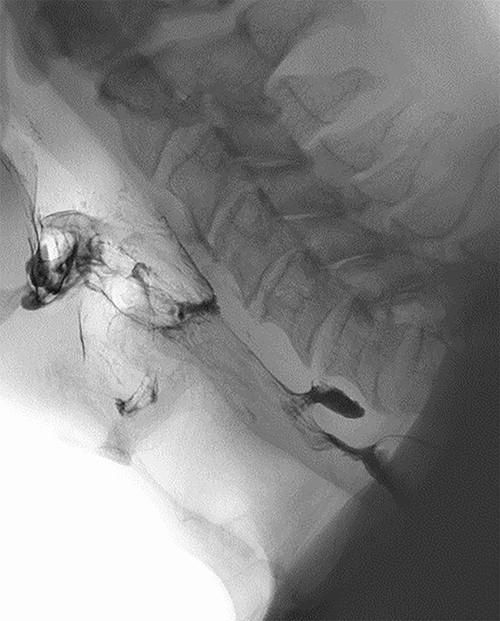

Computed tomography (CT) was performed showing a large, ill-defined mass of which the exact aetiology was initially unclear but suspicious for a primary hypopharyngeal malignancy. Of note, within this mass, a small air collection was observed, containing a 3-mm hyperdense focus (Fig. 2).

CT neck; post-cricoid mass containing an air locule with a 3-mm hyperdense mass (red circle) in the caudal end of this.

There are notable differences between our case and others previously reported. Although acute oesophageal obstruction in ZD has been previously described, it appears to occur exclusively in the presence of large diverticula (>4 cm) which are often impacted with food. Our patient had a small 1.1-cm ZD without food impaction. Identifying the presence of food bolus impaction is critical in these patients due to an increased risk of major complications, such as oesophageal ischemia, perforation or mediastinitis, if the impaction is not addressed within 24 hours of onset [1]. Our patient was previously asymptomatic and had no antecedent symptoms which is in contrast to other published cases. In the present case, it appeared that oesophageal obstruction was caused by localized oedema of the diverticulum triggered by the impaction of an ibuprofen tablet into this, which correlates with the small hyperdense area at the centre of the phlegmon observed on CT (Fig. 2). This is supported by the patient’s history, laryngoscopy findings, imaging and rapid response to intravenous steroids. Due to this, ZD may be an appropriate term. Oral medications, especially ibuprofen, causing oesophageal oedema and obstruction have been described, however, this is usually caused by the large tablet size [10].